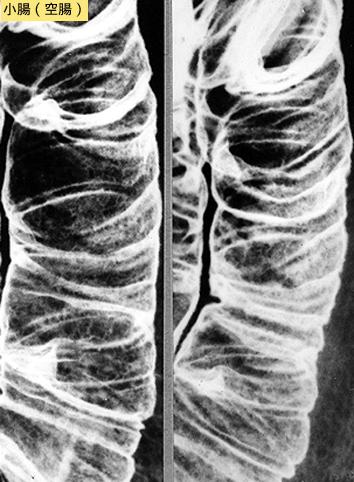

미만성으로 조악한 점막면을 보인 장 아밀로이드증

염증성・궤양성 질환/소화관 유전분증

소장/공장

X-P